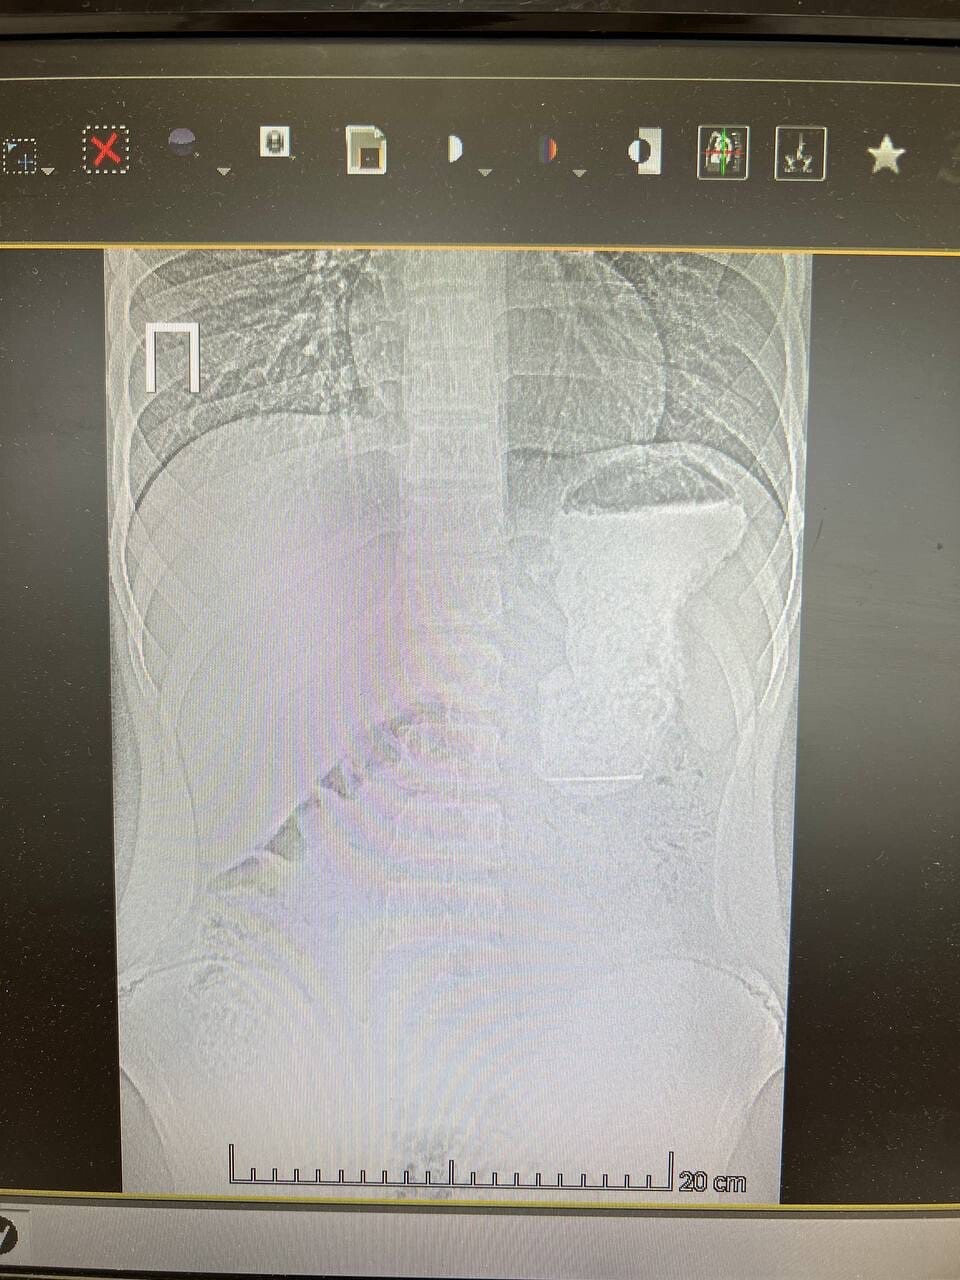

В первом случае мальчик случайно проглотил швейную иглу. Иголка из пищевода попала в желудок, откуда ее успешно достали врачи.

Фото: © пресс-служба КДМЦ